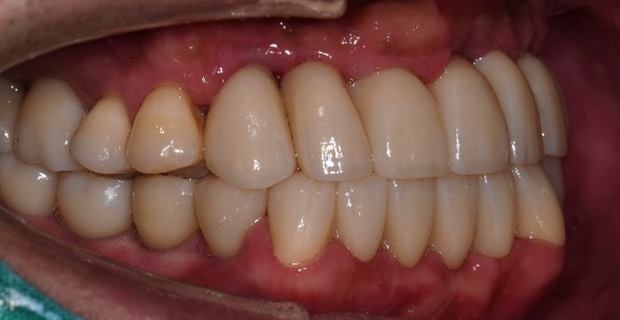

치료 후

전체 치아를 발치하지 않고 보존하여 쓸 수 있는 오른쪽 위 작은 어금니들과 아래쪽 송곳니들을 살려 전체 치아 치료를 해 드렸습니다.

수직고경도 회복하여 심미적으로도 우수하게 좋아졌습니다.